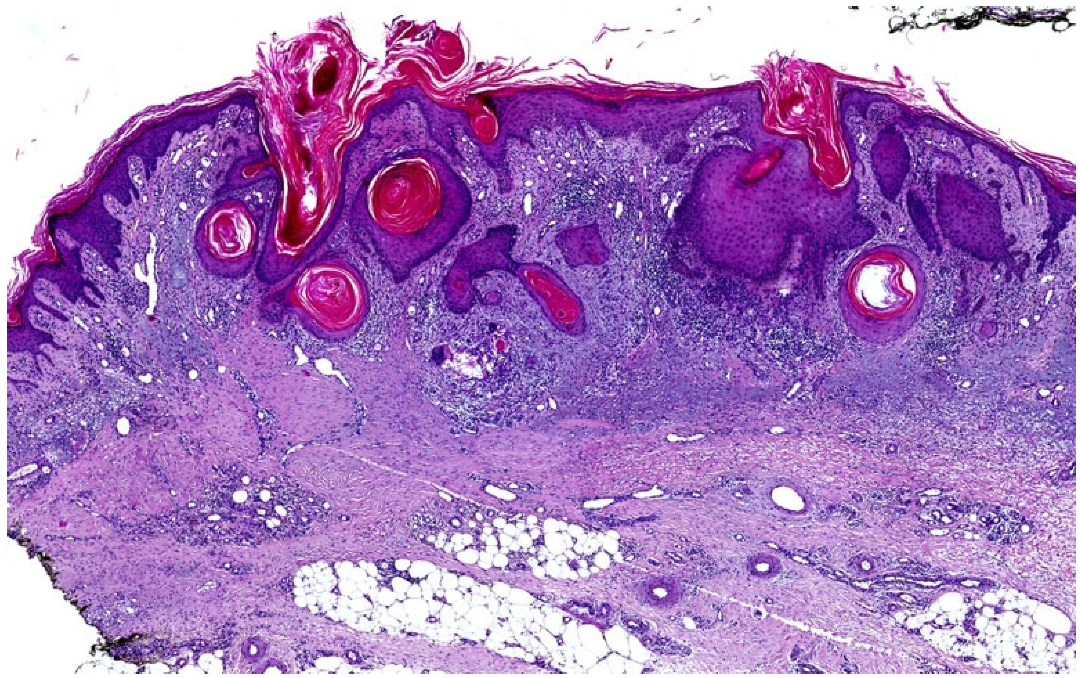

3.2.2. Squamous Cell Carcinoma (SCC)

| SCC | Skin Erythematous-violaceous plaque with a tendency to ulcerate and/or depigment Mucosa Whitish surface with elevated indurated borders; exophytic or endophytic growth patterns with subsequent ulcer formation | Wedge/not wedge-shaped | Dyskeratosis, orthokeratosis | Irregular | Present | Atypical keratinocytes with a variable degree of differentiation: from horn pearl formations to a high number of mitoses and few areas of keratinisation | Depending on staging: locally advanced and rarely metastatic |